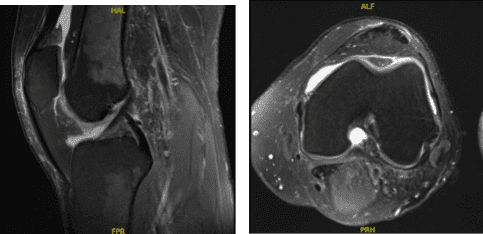

Swelling has decreased. MRI were reviewed and discussed wherein the results have shown 9 x 6 mm full-thickness chondral defect in the midportion of the medial femoral condyle. Focal area of Chondral fissuring and partial-thickness cartilage loss in the central trochlea. Intact medial and lateral meniscus.

MRI-3T Left knee non-contrast